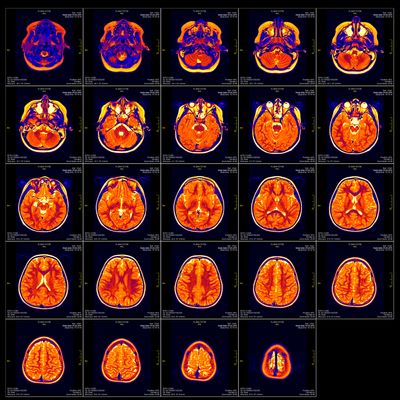

The “normal” temperature of the brain has never actually been defined in humans. Instead, it is generally assumed to be the same as the rest of the body. Previous studies have used data from brain-injured patients, whose brains are directly monitored. Now, brain temperature can be measured in healthy people using magnetic resonance spectroscopy (MRS) – a non-invasive brain scanning technique.

Using MRS, the team behind the new study examined the brains of 40 healthy people – 20 men and 20 women – aged 20 to 40. Measurements were taken three times over the course of a day, making this the first time MRS has been used to track changes in brain temperature throughout the day.

The researchers then created the first-ever 4D map of healthy human brain temperature. Applying this to patients with moderate to severe traumatic brain injury, they found that those without daily brain temperature rhythms were 21 times more likely to die in intensive care.